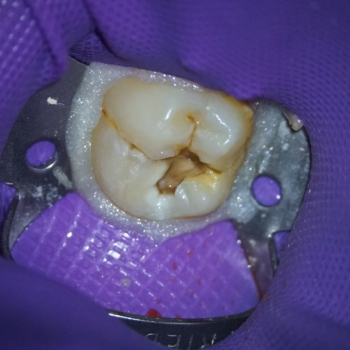

Complete sealing was achieved using a rubber dam, a stainless-steel Clamp, and a light-curing Flowable dam located around the clamp to prevent bacterial contamination of the area to be treated. The caries were removed circumferentially from the coronal towards the cervical margin to limit the movement of bacteria to the pulp tissue space (9). An exploration of the cavity preparation floor showed a pulp exposure (Figs 3 & 4). It is always advisable to explore the cavity preparation floor with an endo explorer, because smaller carious-exposed pulps may be overlooked.

Fig. 3. & Fig. 4. Pulp exposure at the level of the cavity preparation floor, with minimum hemorrhaging that was easy to control.